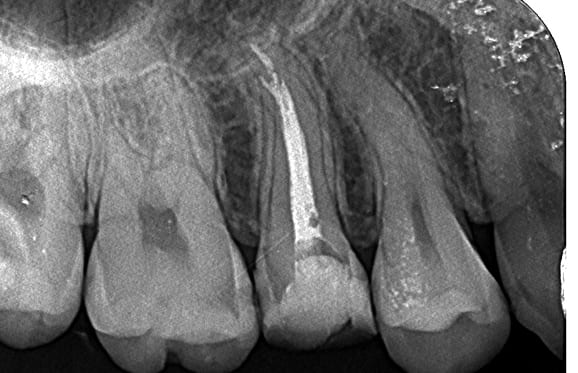

歯を抜かない治療(C4)

不幸にも、虫歯が進行して骨に埋まっている部分の歯(歯根)まで細菌感染が起こってしまった場合(C4)、通常では抜歯が適応治療になります。 しかし、歯根まで虫歯が進行してしまっている場合の多くは痛みが無いのも特徴です。 特に痛みも無いのになんで歯を抜かなければならないかとお思いの患者様も多くいらっしゃいます。 生物学的・医学的には抜歯が適応であったとしても、患者様のご希望と、精密検査の結果から、当院では歯を抜かずに温存する治療も行っております。 もう歯がほとんど残っていないから歯を抜かなければならないと諦めていらっしゃる患者様も、ぜひ一度当院にてご相談、検査をさせて下さい。

根管内の破損器具除去

● 症例1

01 左下7の近心根にエンジンファイルの破折

02 ファイル除去時

※根尖周囲の透過像はまだ残存

03 最終の根充剤を充填

※根尖透過像が小さく治癒方向へ向かっている

● 症例2

01 右上の頬側根に手用ファイルの破折

※若干の打診痛あり